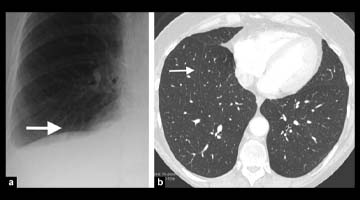

Chest CT: Extensive postoperative subcutaneous emphysema and pneumomediastinum. There is a moderate left-sided pneumothorax after left upper partial lobectomy, despite the presence o left chest tube with its lip at the left ape

Which of the following signs is demonstrated?

- Celery stalk sign

- Drooping lily sign

- Ginko leaf sign

- Holly leaf sign

- Water lily sign